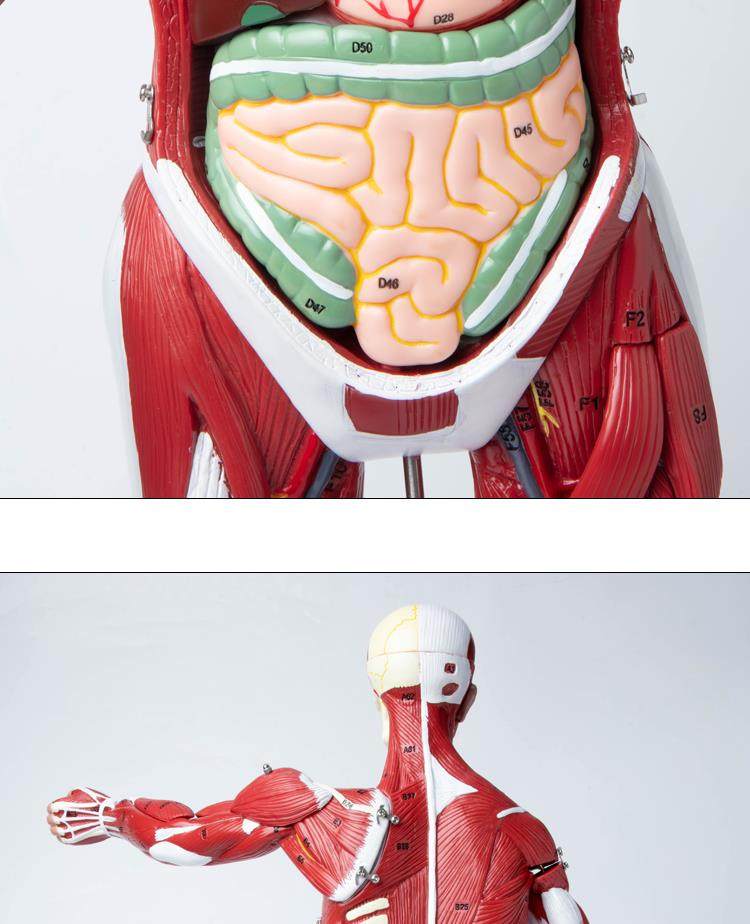

Human Body Muscle Internal Organ Disassembly Anatomy Structure Model Tissue Exercise Artificial Medical Teaching Aids

| Color Classification | 85 Human Muscle Internal Organs Removable Organ,50cm Muscle Model |